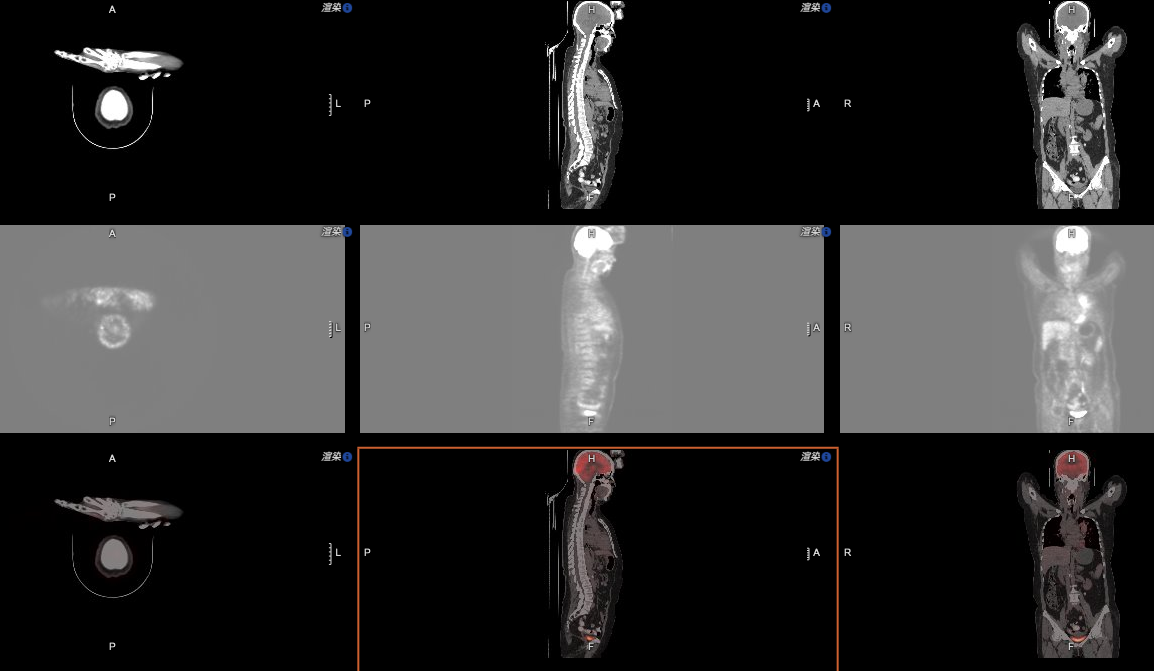

再看這張圖:

相信對(duì)于具備PET/CT的醫(yī)療機(jī)構(gòu)來說,這樣的影像軟件功能同樣是必需的。